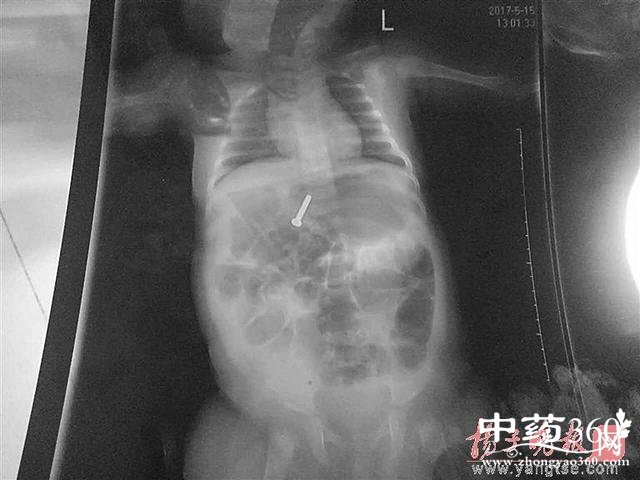

3个月大女婴误吞螺丝钉 消化道异物很危险

近日日,江苏省淮安市一名3个月大的女婴因误吞螺丝钉后出现呼吸急促等症状,情况非常危急,紧急送往医院救治,“女儿现在已无生命危险”,女婴的父亲仲先生在电话里告诉记者,本来应该做手术的,因为螺丝钉已进入女儿肠子里,医生建议在医院等待自行排出。

尖锐物品很危险

如果孩子一不小心吞下了尖锐的异物,因为尖锐物品容易损伤胃肠道就会很危险。如果异物还在孩子的胃里,可以用胃镜取出来,否则如果异物进入小肠再想取出来就只能开刀手术了。但值得注意的是,并不是所有尖锐的异物进入肠子都会对其造成伤害,人的消化道有时甚至能神奇的排出很多异物。